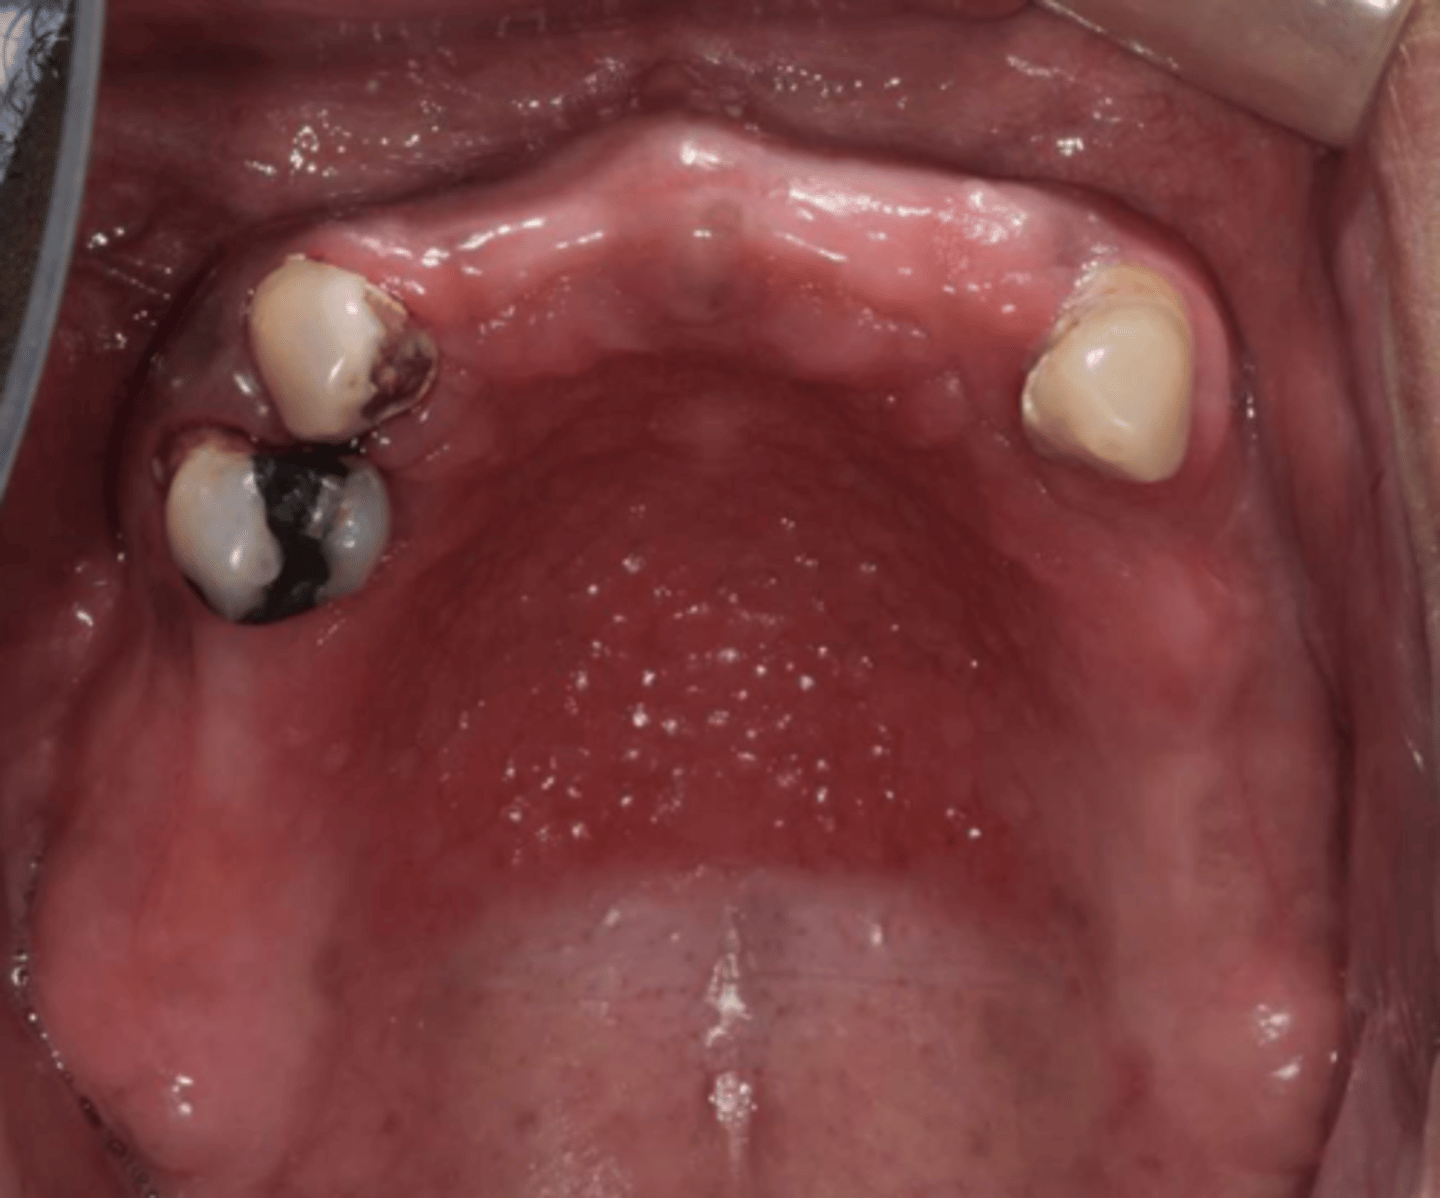

When the patient removed their complete maxillary denture, you see this. They reported wearing their denture to continuously throughout the day & night. What do you suspect?

inflammatory papillary hyperplasia w/ secondary candidal infection

*can tell pt also has candidiasis b/c of erythema

what are these clinical features of?

-hard palate beneath denture base

-pink or pebbly mucosa

-erythema --> suggests secondary candidal infection

inflammatory papillary hyperplasia